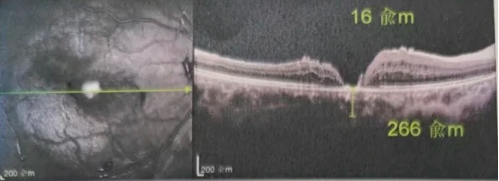

最讓吳爺爺難以置信的是:術后只需保持平躺24小時!第二天復查時,眼底鏡及OCT檢查清晰顯示——那個折磨了他大半年的大裂孔,竟然閉合了!且吳爺爺的右眼視力有了明顯的改善,術后3天已經可以看到 0.15。

黃斑裂孔

李海波博士后表示:如果來得更早一些,他的視力還可以恢復得更好。但現在的治療結果對于經歷過兩次失敗手術和漫長煎熬的他而言,已是奇跡。

李海波博士后指出:遠周邊移植自體內界膜覆蓋技術尤其適合那些反復多次手術裂孔仍未閉合,以及后極部沒有健康內界膜可用的復雜病例。與傳統(tǒng)手術相比,該技術具有諸多獨特之處:

首先,它改變了獲取內界膜組織的方式,選取遠周邊內界膜組織,并且采用正向覆蓋的方法。這一創(chuàng)新極大地提高了裂孔的閉合率,解決了后極部無健康內界膜可用的治療難題。

其次,該技術無需填充氣體或硅油,避免了由此帶來的一系列并發(fā)癥問題。

更為關鍵的是,患者術后無需再忍受長時間的俯臥煎熬,僅需平躺24 小時,裂孔就能實現閉合,大大提升了患者的舒適度,也降低了其他并發(fā)癥的發(fā)生風險。